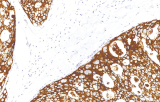

L’immunoistochimica (IHC) con anticorpi primari CE/IVD è essenziale per una diagnosi e classificazione accurata sia delle malignità ginecologiche che mammarie. Questi anticorpi consentono la rilevazione precisa di marcatori tumorali e proteine cellulari, supportando la diagnosi differenziale e guidando strategie terapeutiche personalizzate.

Gli anticorpi primari contro il recettore degli estrogeni (ER), recettore del progesterone (PR), HER2 e Ki-67 rimangono il pilastro della classificazione e delle decisioni terapeutiche nel cancro al seno. Questi anticorpi sono validati clinicamente e marcati CE/IVD per garantire una rilevazione affidabile e riproducibile dei biomarcatori – cruciale per guidare la terapia ormonale e le strategie di trattamento mirato.